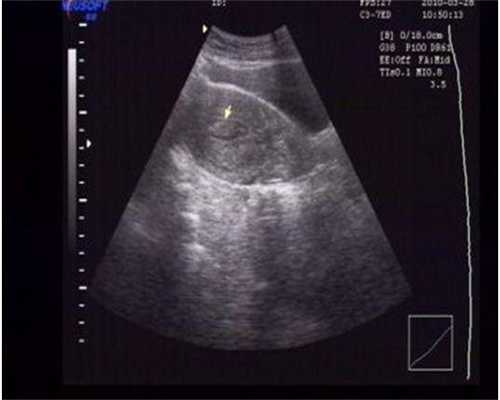

试管(抗拮剂方案)促排中